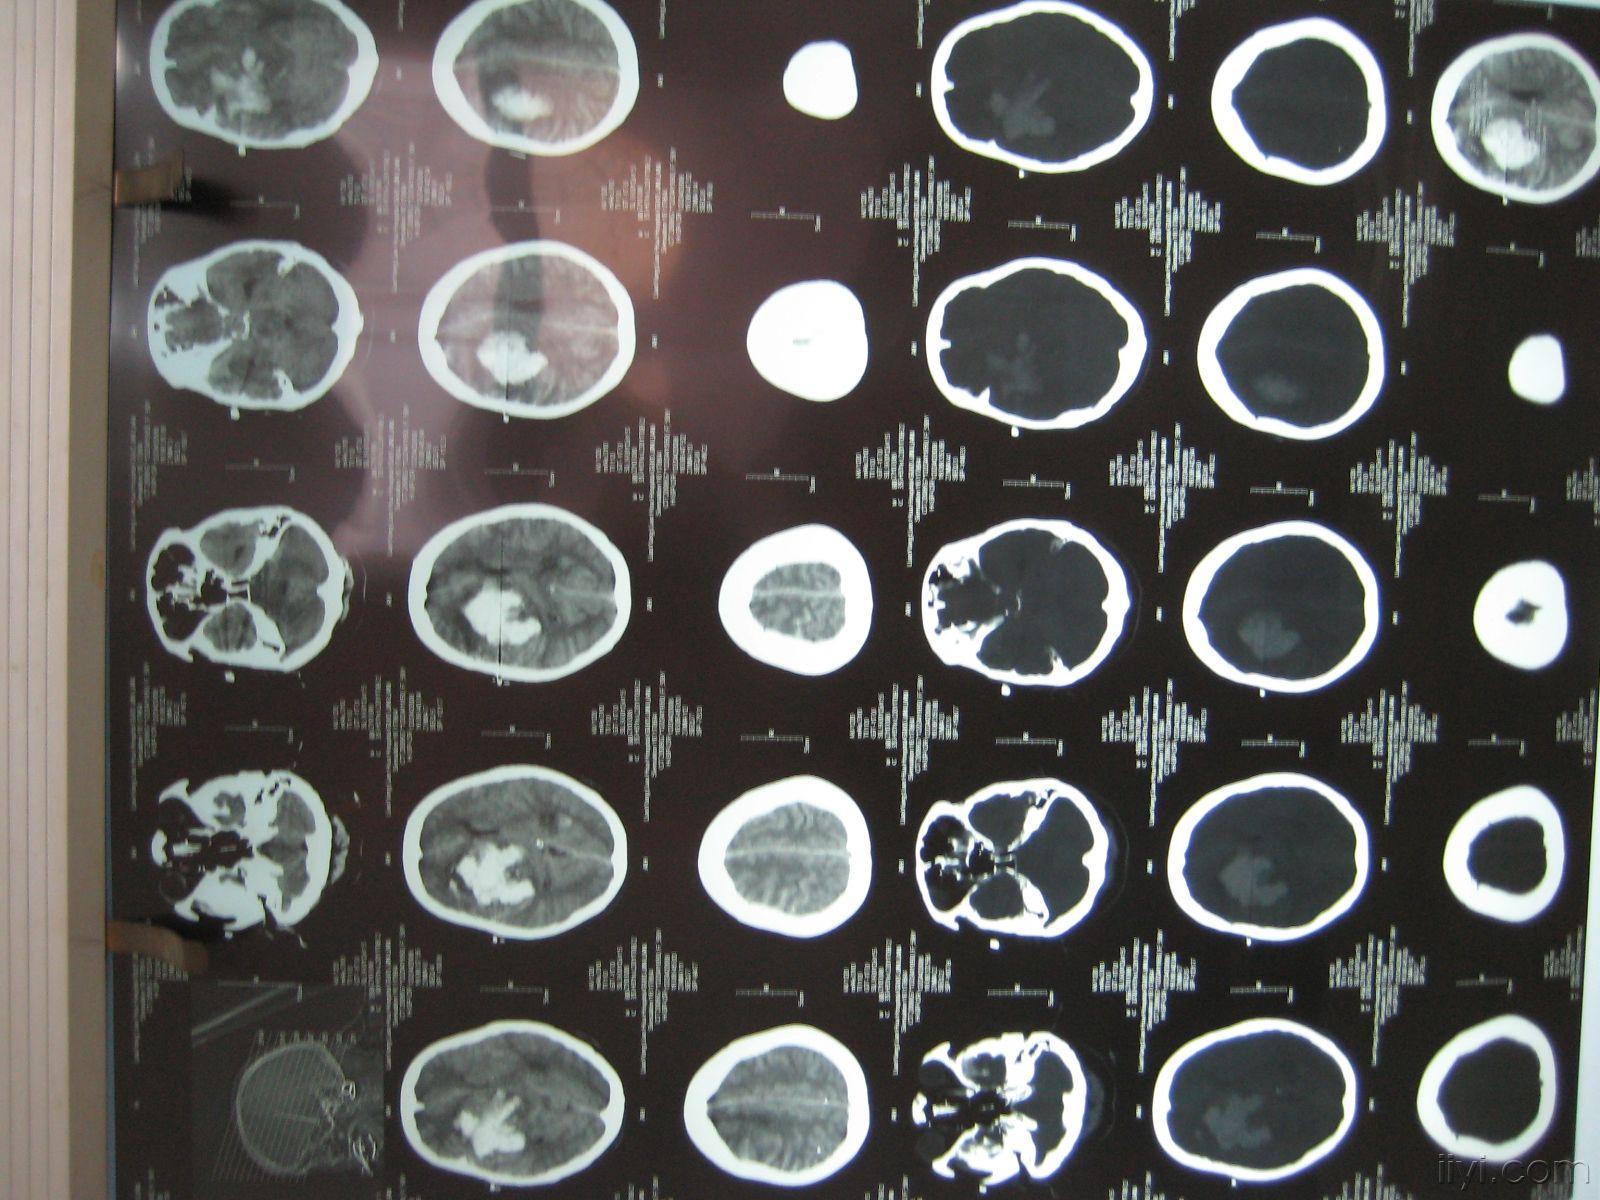

头部ct图片 血块

男性,60岁,失语,偏瘫1小时入院,入院后急查头部ct提示:左侧基底节脑

青年男性,突发意识不清2小时入院,头ct提示顶枕叶脑出血.

患者8天前无明显诱因突发头晕入院,头ct示:脑出血